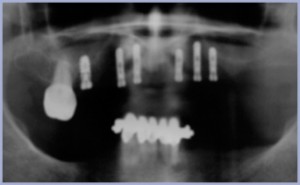

Ad una prima visita, avvalorata successivamente da una radiografia opt (fig. 1), si evidenziarono problemi di origine parodontale endodontica e cariosa, solamente il 1.6 era in buone condizioni (figg. 2-4). La paziente aveva espresso il desiderio di essere riabilitata con una protesi fissa, senza dover sottoporsi a dei trattamenti molto lunghi ed invasivi. La prima fase è stata la bonifica dell’arcata con l’estrazione dei residui radicolari, il riempimento degli alveoli con del biomateriale (Fisiograf Gel) e la trasformazione del suo vecchio lavoro in una protesi parziale rimovibile.

- Fig. 1